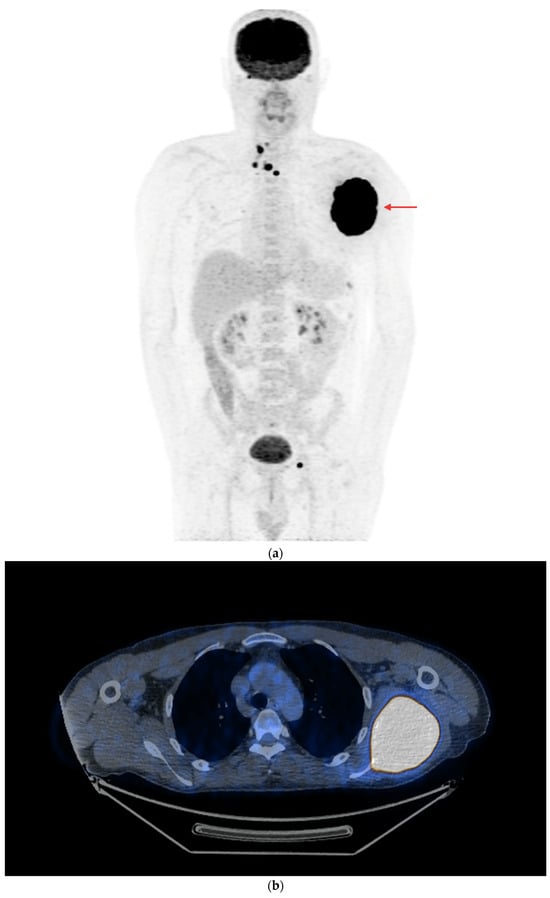

Figure 6.

PET/CT with [18F]FDG (a) Maximum-intensity projection (MIP). (b) Axial fusion projection. Multiple metastatic lesions are visible in the mediastinal lymph nodes, with a small metastasis to the left pelvic bone and an extensive tumor in the left scapula (red arrow) is visible with high [18F]FDG accumulation (the lesion was confirmed using a core needle biopsy as metastasized DTC). The patient was disqualified from surgical treatment and qualified for TKI therapy (initially sorafenib, then cabozantinib due to progression). The patient died in December 2023 (i.e., 51 months after the DTC diagnosis and 37 months after the confirmation of non-iodine-avidity disease).